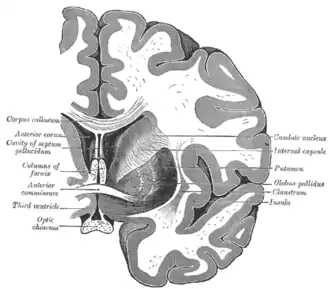

Structure

Along with the putamen, the caudate forms the dorsal striatum, which is considered a single functional structure; anatomically, it is separated by a large white-matter tract, the internal capsule, so it is sometimes also described as two structures—the medial dorsal striatum (the caudate) and the lateral dorsal striatum (the putamen). In this vein, the two are functionally distinct not because of structural differences, but merely because of the topographical distribution of function.

The caudate nuclei are near the center of the brain, sitting astride the thalamus. There is a caudate nucleus in each hemisphere of the brain. Each nucleus is C-shaped, with a wider "head" (caput in Latin) at the front, tapering to a "body" (corpus) and a "tail" (cauda). Sometimes a part of the caudate nucleus is called the "knee" (genu).[6] The caudate head receives its blood supply from the lenticulostriate artery; the tail of the caudate receives its blood supply from the anterior choroidal artery.[7]

The head and body of the caudate nucleus form part of the floor of the anterior horn of the lateral ventricle. The body travels briefly towards the back of the head; the tail then curves back toward the anterior, forming the roof of the inferior horn of the lateral ventricle. This means that a coronal section (on a plane parallel to the face) that cuts through the tail will also cross the body and head of the caudate nucleus.